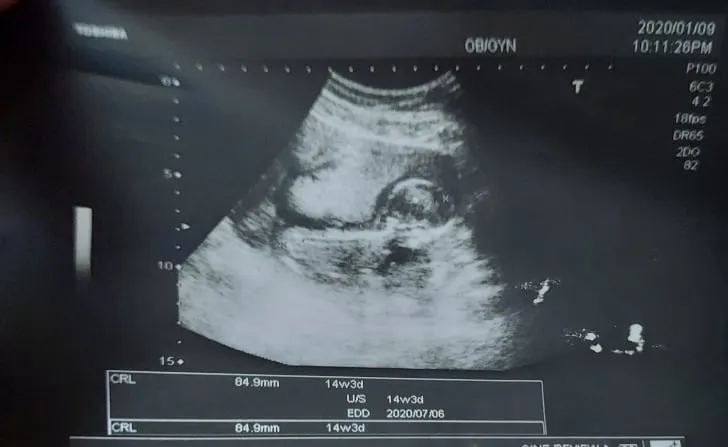

2020.1.4(六)PM2:03

原來住哪裡真的很重要(因為我們剛搬家),心情都好起來了,為了未來產檢和生產順利,我們迅速地找房搬家,我的2020請繼續給力,感謝天主一路帶領,謝謝為我們祈禱的人,希望下週的產檢也能順利,每天睡覺都好怕小鼻鼻被我壓到窒息,而且又聽不到他的心跳,每天都在想,哈囉還活著嗎,睡覺半夜會被嚇醒說,天啊 我是仰睡,是不是太緊張啊?